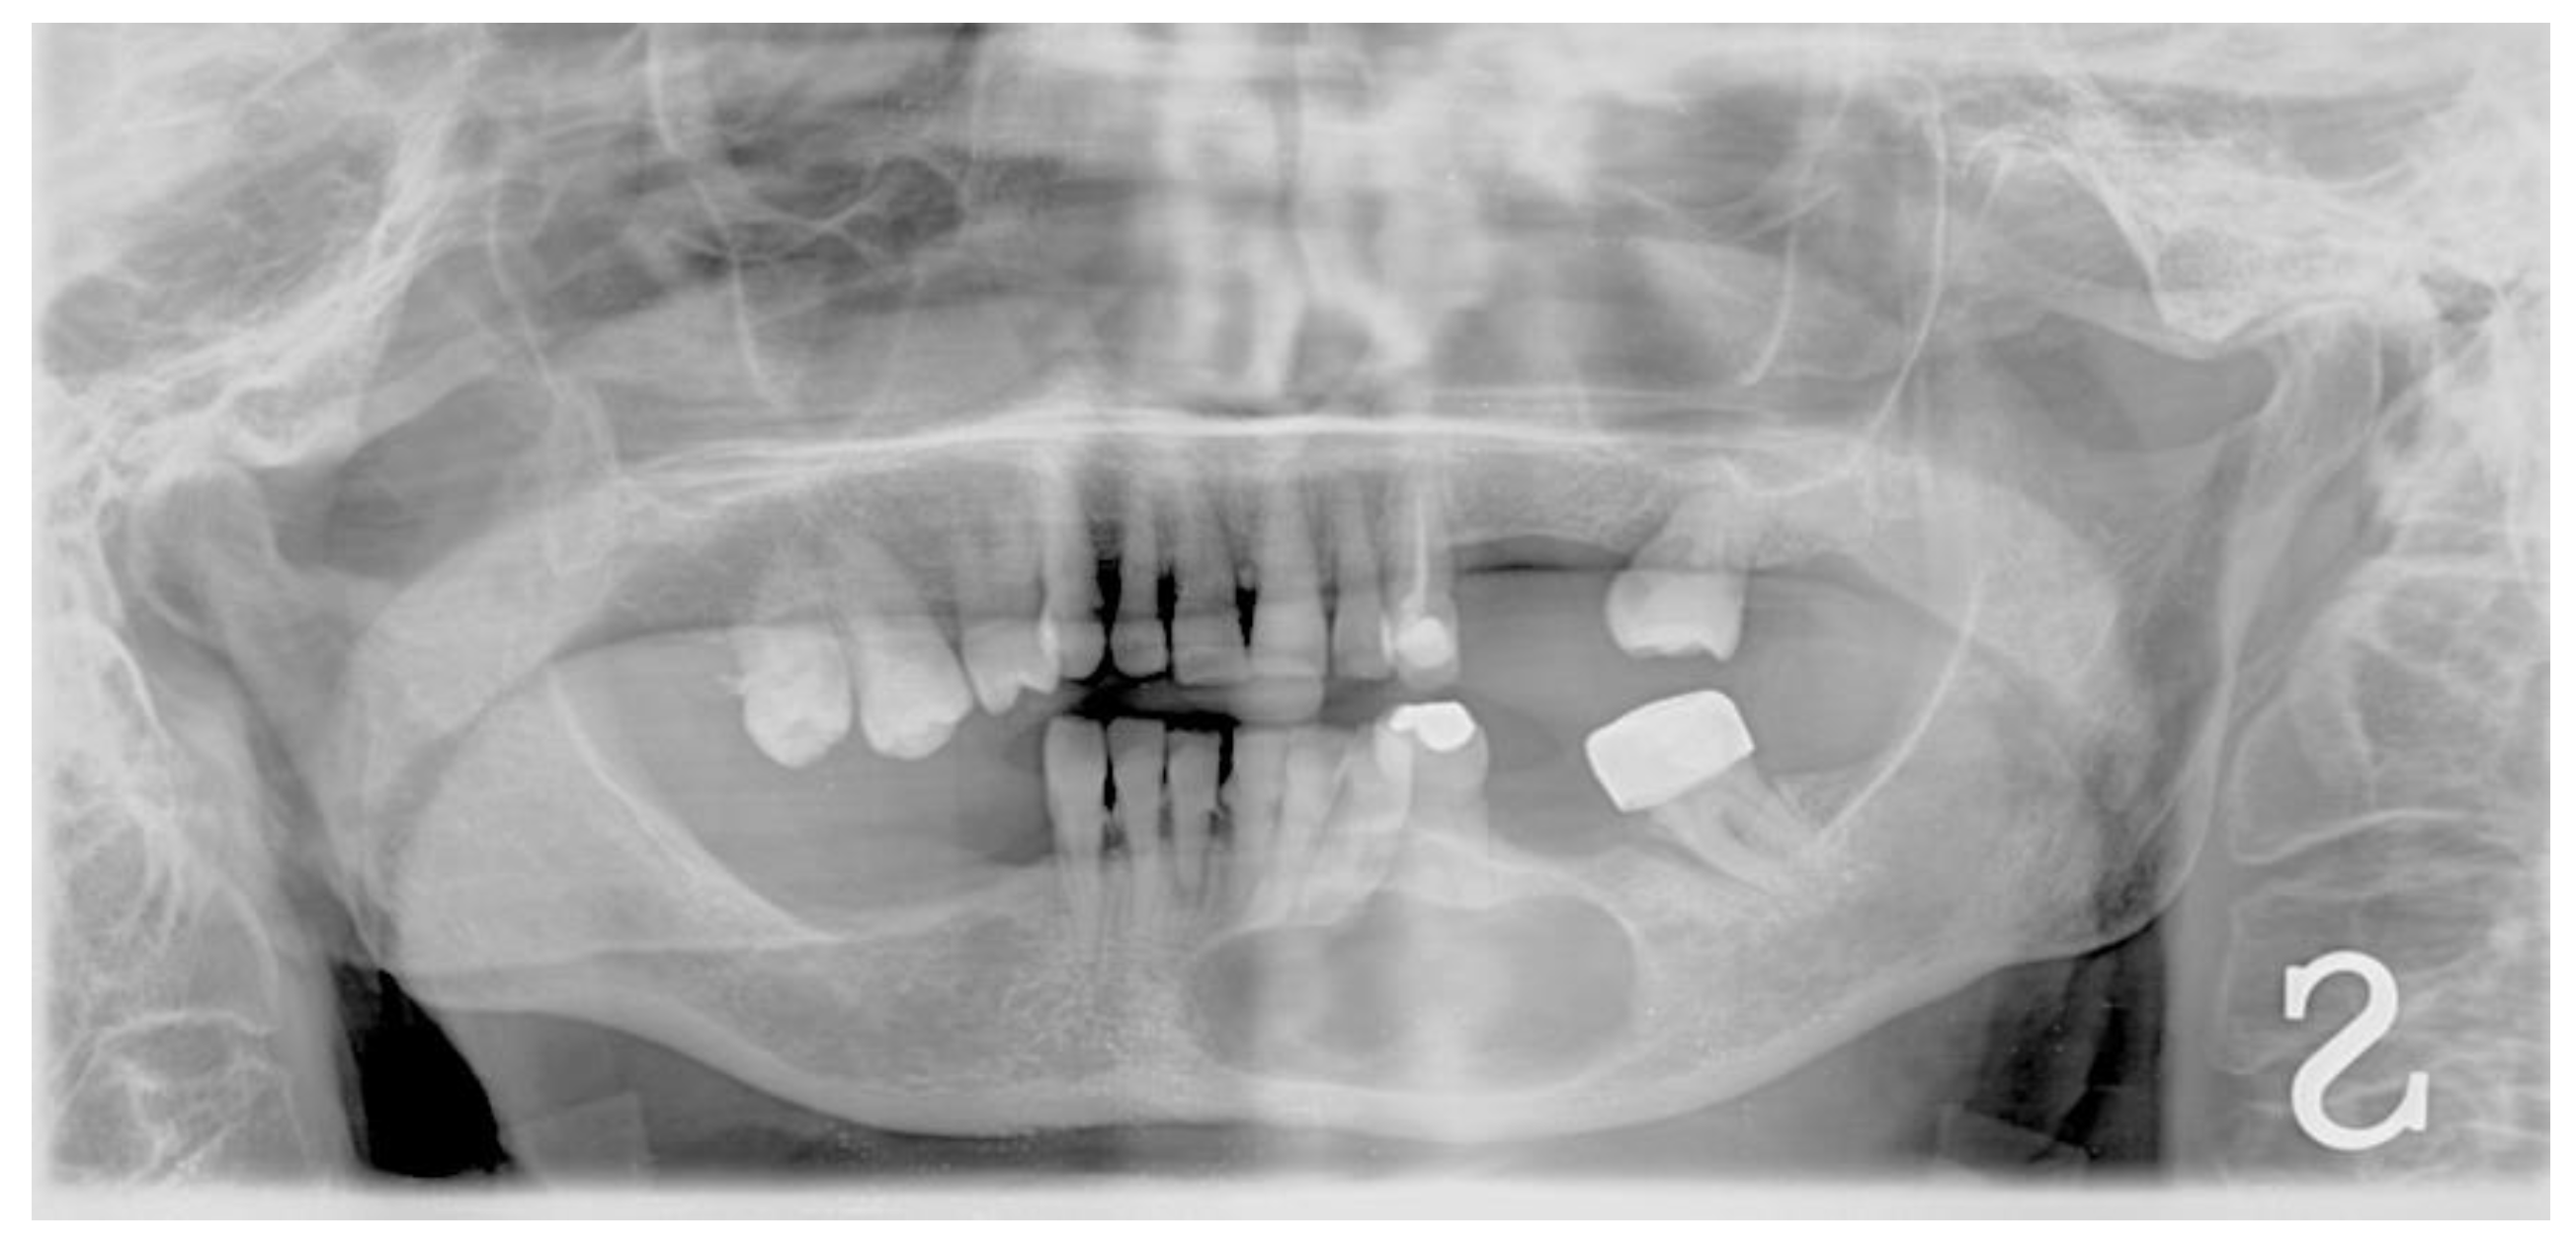

2. Materials and Methods

3. Results